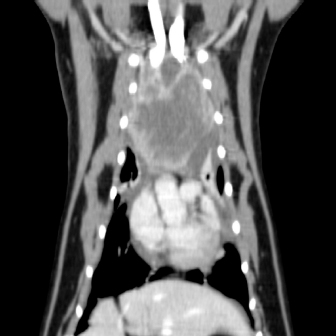

On physical examination, the cat had an unkept coat, reduced respiratory sounds cranially, and persistent stridor, but was otherwise bright and ambulatory. Computed tomography (CT) was performed using a Phillips Brilliance six slice CT. Multiphase contrast-enhanced CT images of the head, thorax, and abdomen were acquired with the cat in sternal recumbency (Figs. 1 and 2). A cranial mediastinal mass measuring 60 × 40 mm causing dorsal tracheal displacement toward the right was identified. With contrast administration, there was moderate enhancement of the periphery (+60 Hu) and poor central enhancement (+10 Hu). There was moderate to marked compression of the cranial vena cava, with a focal intraluminal contrast-filling defect at the cranial aspect of the vena cava just caudal to the mass. Here, the path of the cranial vena cava could not be completely traced, suggesting almost complete compression or invasion. There was no evidence of subcutaneous edema of the head or cervical region. Moderate volume of pleural fluid was bilaterally present. Multifocal, slightly branching soft tissue conglomerates largely following the bronchi of the caudal lobes toward the apex was noted, most likely to be bronchial disease with bronchiolar consolidation. Pulmonary metastatic neoplasia was considered to be unlikely. Surgical resection in the form of debulking was recommended on the basis that the large cranial mediastinal mass was most likely the cause of the cat’s clinical signs, and that reduction of gross disease should improve survival time as well as being more responsive to adjunctive treatment with chemotherapy. The cat was then started on mirtazapine (1.875 mg orally every 48 hours) and prednisolone (5 mg orally every 24 hours).

Fig. 2. Computerized tomography of the cranial mediastinal mass (coronal plane).